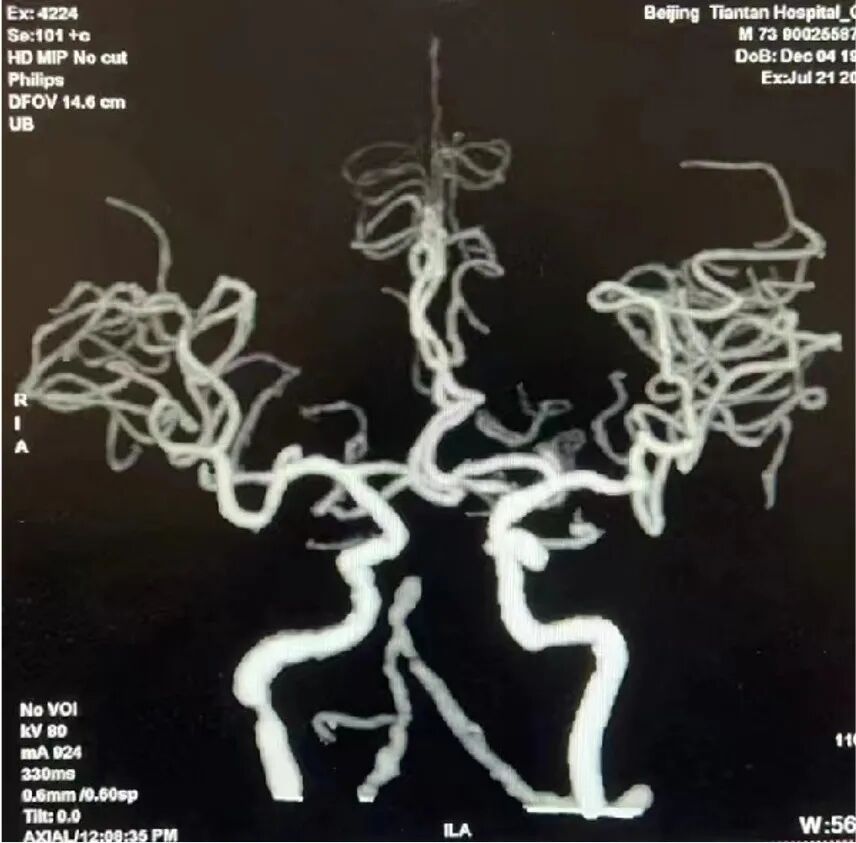

术前影像学检查结果

造影显示基底动脉远端闭塞,建立血管内治疗通路:Locaste长鞘同轴带领Skathi远端通路导管到位。